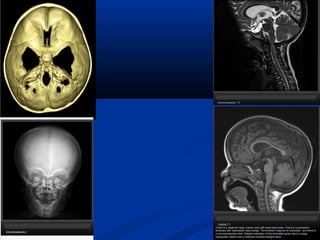

CHIARI MALFORMATION �The Chiarimalformations are a group of hindbrain herniation syndromes initially described by Austrian pathologist Hans Chiari in 1891. �Types of Chiari malformations : �Type I: Caudal descent of cerebellar tonsils in cervical spine. Osseous anomalies of posterior skull base and spine. It presents in early adulthood rather than at birth. Associated with syringomyelia in 50 to 70%.

• 112.

ARNOLD-CHIARI MALFORMATION I Present inadulthood ="cerebellar tonsillar ectopia" Herniation of cerebellar tonsils > 5mm below a line connecting Basion with Opisthion (= foramen magnum) Causes: • small posterior fossa, •cerebellar overgrowth, •disproportionate CSF absorption Associated with: 1. Syringohydromyelia (30-56%) 2. Hydrocephalus (25-44%) 3. Malformation of skull base NECT: Effaced Posterior Fossa cisterns "Crowded" Foramen Magnum Lateral/3rd ventricles usually normal

• 114.

ARNOLD-CHIARI MALFORMATION II Radiography Lucken shadel-Craniolacunia = Lacunar Skull = mesenchymal dysplasia of calvarial ossification Absent / Hypoplastic posterior arch of C1 Myelography Tethered cord NECT Small posterior fossa Large, funnel-shaped foramen magnum "Scalloped" petrous pyramid, "notched" clivus Absent falx cerebelli